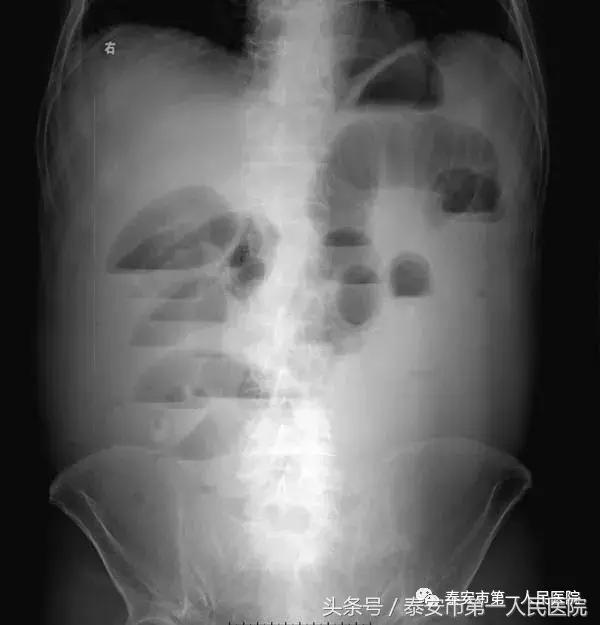

(十三)腹部X线平片如有十二指肠或小肠节段性扩张或右侧横结肠段充气梗阻,常提示有腹膜炎及肠麻痹的存在。前者称为警哨肠曲征,后者称为结肠切割征,多与重症急性胰腺炎有关。